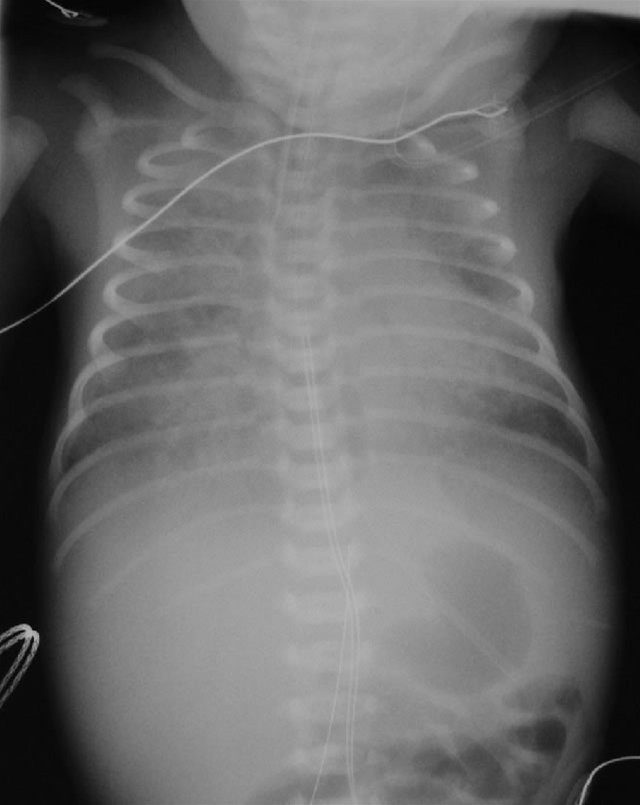

Mekonium aspirationssyndrom.

• Rtg. thorax viser plettede atelektaser eller konsolidering med fortætning af lungevæv